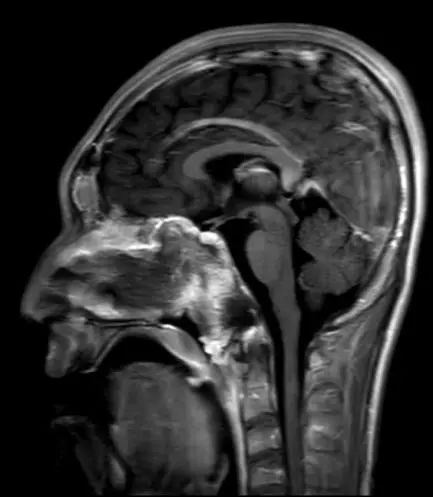

术后MRI显示肿瘤切除满意